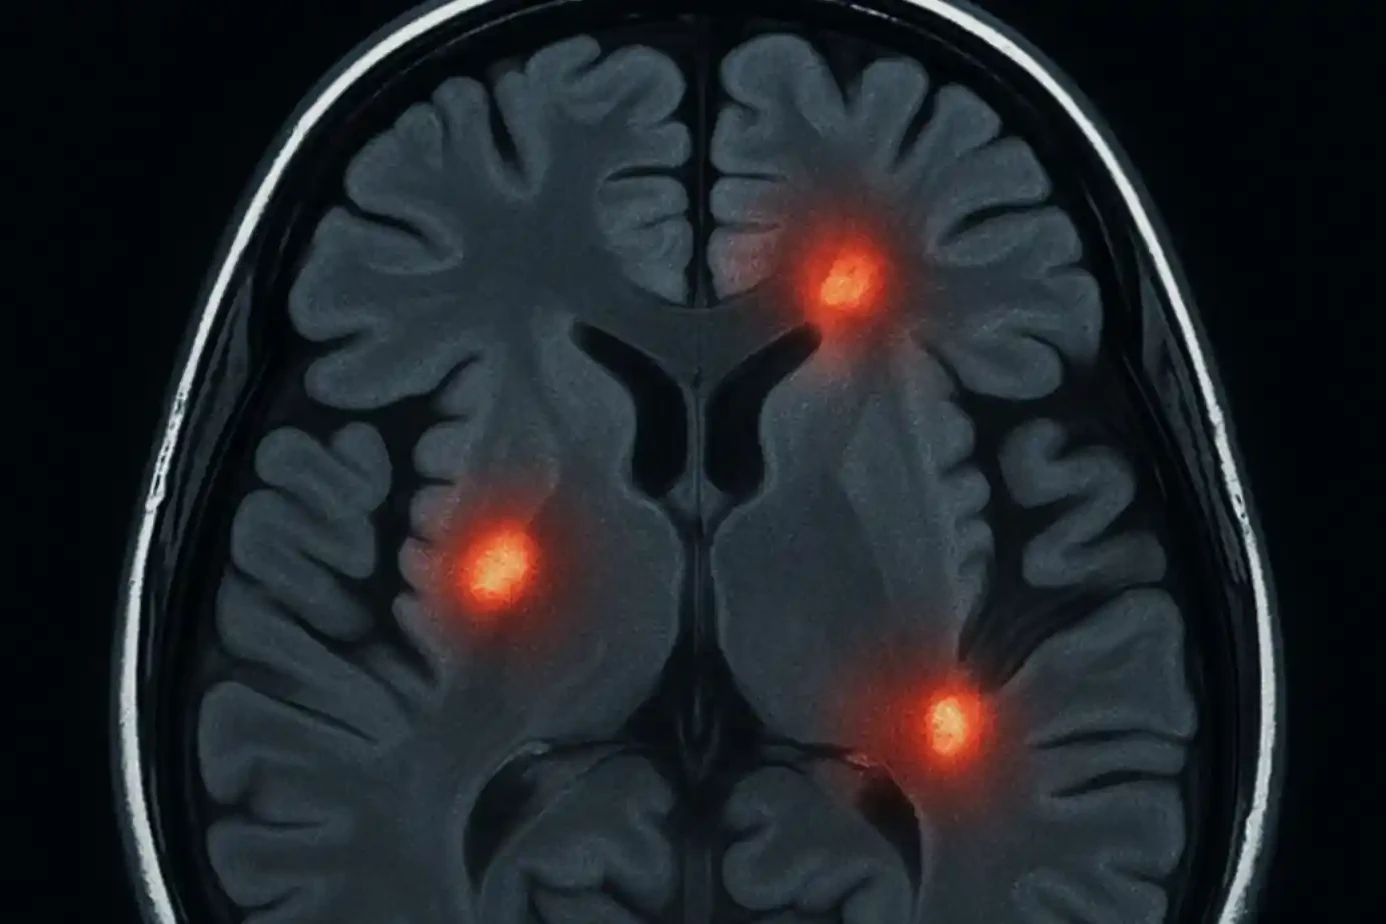

Migraine and Brain Lesions

What Are Brain Lesions? A brain lesion is an area where brain tissue is damaged. The damage can…

Brain Lesions: Causes, Symptoms, Treatments

Brain lesions are areas of damage in the brain tissue, and understanding them is crucial for your…